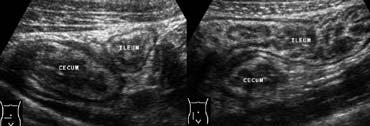

Hình 6. Nam giới 39 tuổi bị viêm hồi manh tràng do vi khuẩn. A và B, Siêu âm cho thấy dày thành mức độ vừa của hồi tràng đoạn cuối và manh tràng, được bao quanh bởi mô mỡ bình thường không viêm. Hạch bạch huyết mạc treo phóng to mức độ vừa cũng hiện diện (không hiển thị).

Viêm hồi manh tràng do vi khuẩn

Do hạch bạch huyết phóng to cũng thường gặp trong viêm ruột thừa, ruột thừa bình thường phải được quan sát rõ ràng trên các phương tiện chẩn đoán hình ảnh trước khi xác định chẩn đoán viêm hạch mạc treo. Viêm ruột kết do nhiễm trùng có thể gây ra các triệu chứng nhẹ giống viêm dạ dày ruột do virus thông thường, nhưng cũng có thể biểu hiện lâm sàng với các đặc điểm không thể phân biệt với viêm ruột thừa [4].

Biểu hiện sau này có thể xảy ra trong viêm hồi manh tràng do vi khuẩn, gây ra bởi Yersinia, Campylobacter hoặc Salmonella. Các phương tiện chẩn đoán hình ảnh cho thấy dày thành hồi tràng đoạn cuối và manh tràng mà không có viêm mô mỡ xung quanh (Hình 6), và hạch bạch huyết mạc treo phóng to mức độ vừa.